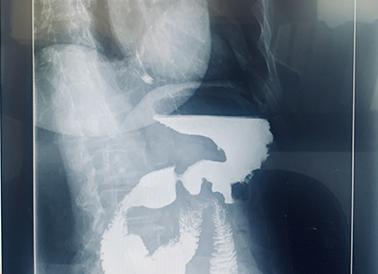

Исследование пищевода или желудка выполняется врачом рентгенологом. Заключается оно в том, что выпитая пациентом взвесь бария постепенно обволакивает стенки полого пищеварительного органа, который изучается на предмет локализации в нем патологических дефектов. Все это время специалист делает снимки и выводит реальную картинку на экран монитора. Поэтапно проведение процедуры выглядит следующим образом:

• выпивается глоток плотной смеси сульфата бария, что необходимо для того, чтобы записать акт глотания;

• следующим этапом больному человеку необходимо сделать несколько глотков контрастного вещества, одновременно поворачиваясь в разные стороны. Это позволяет проследить за продвижением бария по пищеводу и сделать прицельные снимки в нескольких положениях;

• затем пациента помещают на рентгеновский стол и повторяют процедуру в лежачем положении. Эта тактика позволяет оценить перистальтику пищевода и выявить желудочно-пищеводный рефлюкс или грыжу пищеводного отверстия диафрагмы;

• следующие несколько глотков контрастной взвеси позволяют специалисту сделать прицельные снимки в те моменты, когда обнаруживается патология пищеварительных органов.

Рентгеноскопия желудка и пищевода выполняется исключительно с контрастированием, так как на обзорном снимке увидеть пораженный орган невозможно. Для облегчения визуализации пищеварительных органов принято применять сульфат бария. В том случае, когда проводится исследование верхних отделов желудочно-кишечного тракта, специалисты отдают предпочтение жидкой взвеси этого препарата. Рентген пищевода с густым контрастом проводится только в том случае, если необходимо все отделы этого пищеварительного органа осмотреть в деталях.

Связано это с тем, что смесь, имеющая большую плотность, стекает по стенкам пищеводного канала значительно медленнее. Она успевает прокрасить полностью все складки этого органа и выделить имеющиеся в нем патологические дефекты. Хотя и считается, что проглоченный контраст полностью безопасен для организма, нежелательные последствия и осложнения все-таки имеют место изредка проявиться:

Исследование проводится в вертикальном и горизонтальном положении пациента поочередно. Смесь с пищевода при расслаблении сфинктера переходит в желудок, заполняя пространство между его складками. Врач проводит пальпацию для более равномерного распределения вещества.

В норме барий проходит по пищеводу, затем перистальтической волной переносится в его нижней отдел. Когда раскрывается кардиальный жом, барий проникает в желудок. При отсутствии нарушений вещество свободно и равномерно распределяется по глотке и пищеводе, слизистая при этом выглядит неизмененной.